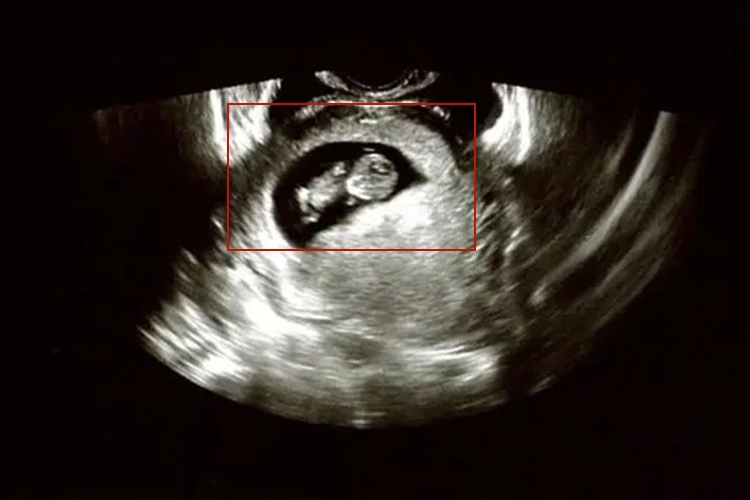

怀孕67天胎儿初具人形,身长达4cm,头的大小约占胎体一半,五官已能辨认。

怀孕67天约为胎儿10周末时,属孕早期,胎儿初具人形,身长达4cm,头的大小约占胎体一半,五官已能辨认,四肢已具人形,形状像扁豆荚,早期心脏已经形成,B超检查可见胎心搏动。